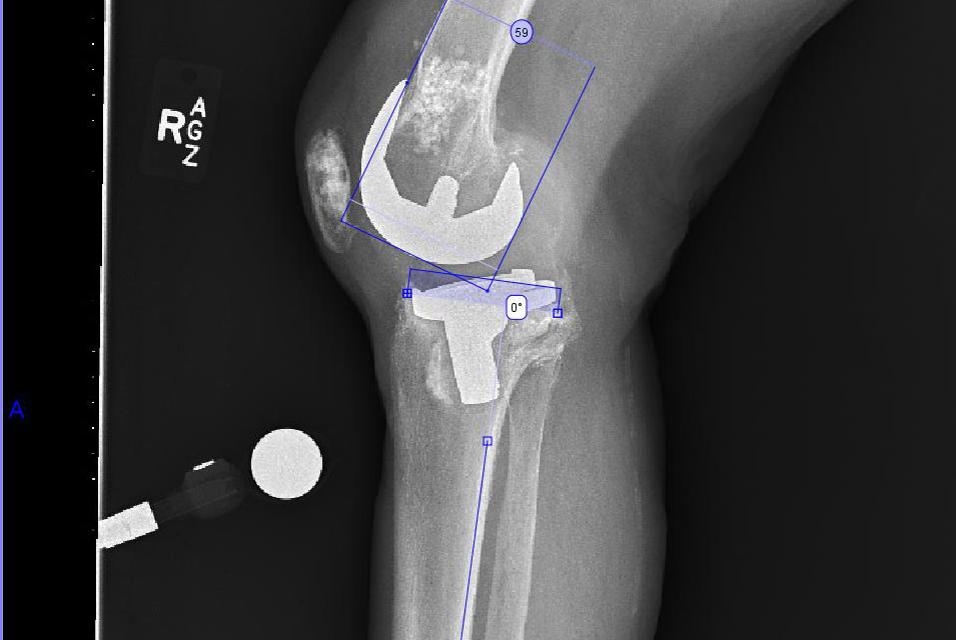

A physical examination revealed anteroposterior and medial instability with 10-degree hyperextension to 90-degree flexion. Due to gross component loosening on radiographs and functional limitations, a revision knee procedure was planned.

- It was identified that stemmed components were required for both the tibia and the femur.

- We determined that a tibial augment was required as a result of the varus failure of the tibial component and medial tibial bone loss.

- The offset value provided by the software identified that an offset tibial component was required to avoid an abutment of the cortex by the tibial stem.

Joint line:

- We were able to assess how the preoperative plan would affect the joint line and determined that it would maintain it reasonably well.

In revision cases, the existing femoral and tibial component positions are ignored, and bony landmarks are used to identify where to place the femoral and tibial preoperative planning tools.

There appeared to be a significant amount of osteolysis in the femur. Metaphyseal cones or allografts were considered for bone stock restoration/substitution, but were eventually not needed.

The preoperative planning software allows the width of the femur and tibia to be assessed for proper component sizing, which is important as size is the primary focus, rather than angles. Intramedullary guides are used to restore the mechanical axis. Also key with revisions is identifying where the articular surfaces of the revision components would lie, in relation to the shaft. Further, it is helpful to preoperatively determine the offset of the tibial component (more than that of the femoral component), as this can help intra-operatively reduce the need for trialing of various tibial stems.

The tibial AP axis indicates that an offset tibial stem will be needed.

During the templating stage, varying stem sizes are trialed to ensure bony defects will be bypassed by at least two cortical diameters.

Templating on the lateral view permits assessment of the proposed joint line. Augments can readily be added to the distal femur or tibia if the templated polyethylene size is too large, or the joint line is too high or low, based on bony landmarks.